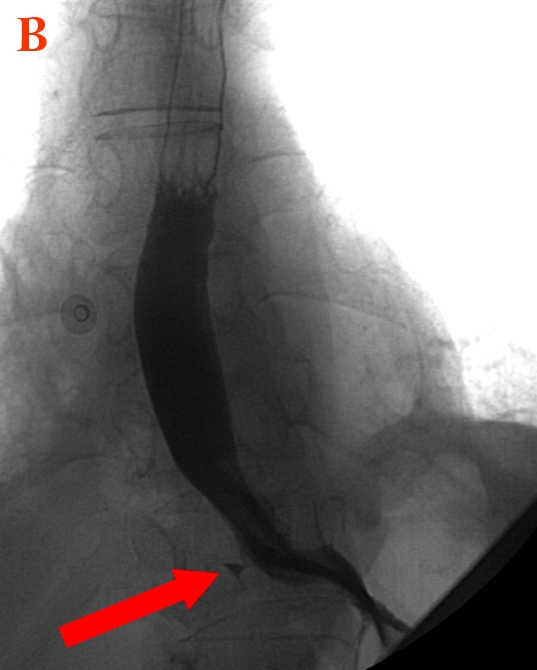

This patient with exertional arm pain (likely claudication), systemic symptoms, and pulse deficits has typical features of Takayasu arteritis, a chronic large artery vasculitis that predominantly affects Asian women age <40. It primarily involves the aorta and its branches and is characterized by mononuclear infiltrates and granulomatous inflammation of the vascular media, leading to arterial wall thickening with aneurysmal dilation or narrowing and occlusion.

Initial symptoms are nonspecific (eg, fever, arthralgias, weight loss). As the disease progresses, vascular involvement with arterio-occlusive manifestations (eg, claudication, distal ulcers) may develop, particularly in the upper extremities. Examination findings include blood pressure discrepancies, pulse deficits, and bruits. Patients commonly have anemia and elevated inflammatory markers (eg, erythrocyte sedimentation rate, C-reactive protein). Chest x-ray can reveal aortic dilation and a widened mediastinum, and CT and MRI may reveal thickening of large artery walls and narrowing of the arterial lumen. Initial treatment includes systemic glucocorticoids.